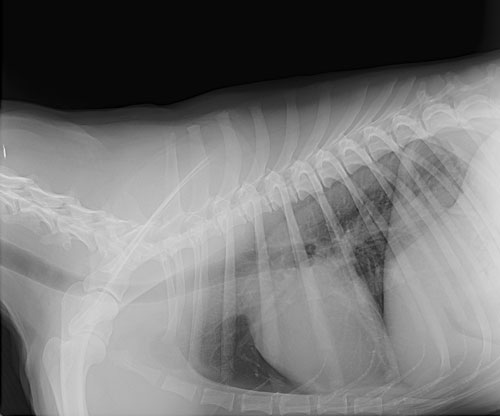

Radiographs can be used to diagnose fractured bones, intestinal foreign bodies, bladder stones, and can be a valuable tool in cardiac disease.